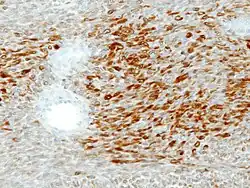

Double contingent épithélial et conjonctif. HE, x400.

Immunohistochimie

_S-100.jpg)